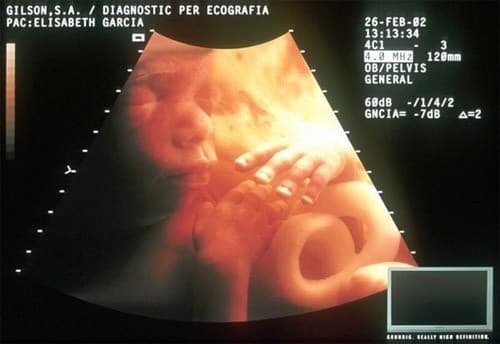

Siêu âm 4 chiều (4D)

Phát triển hơn siêu âm 3D, có thể tự động ghi hình chân dung bé trong bụng mẹ chính xác và hình ảnh thật nhất, giúp cho việc kiểm tra, theo dõi sức khỏe thai nhi, giúp thai phụ yên tâm hơn.

Siêu âm màu 4D còn giúp xác định tuổi thai, phân tích phát triển bào thai; phát hiện bất thường thai nhi; phát hiện vấn đề về cấu trúc của tử cung, bất thường nhau thai, chảy máu bất thường, phát hiện khối u buồng trứng, u xơ, vị trí nhau thai, ghi hình chuyển động của thai nhi, chụp hình các cơ quan nội tạng của cơ thể thai nhi.